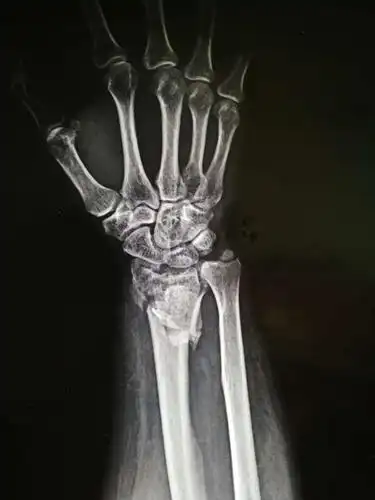

一例桡骨远端粉碎性骨折

桡骨远端粉碎性骨折

一例儿童桡骨远端粉碎性骨折

桡骨远端粉碎骨折 波及关节面